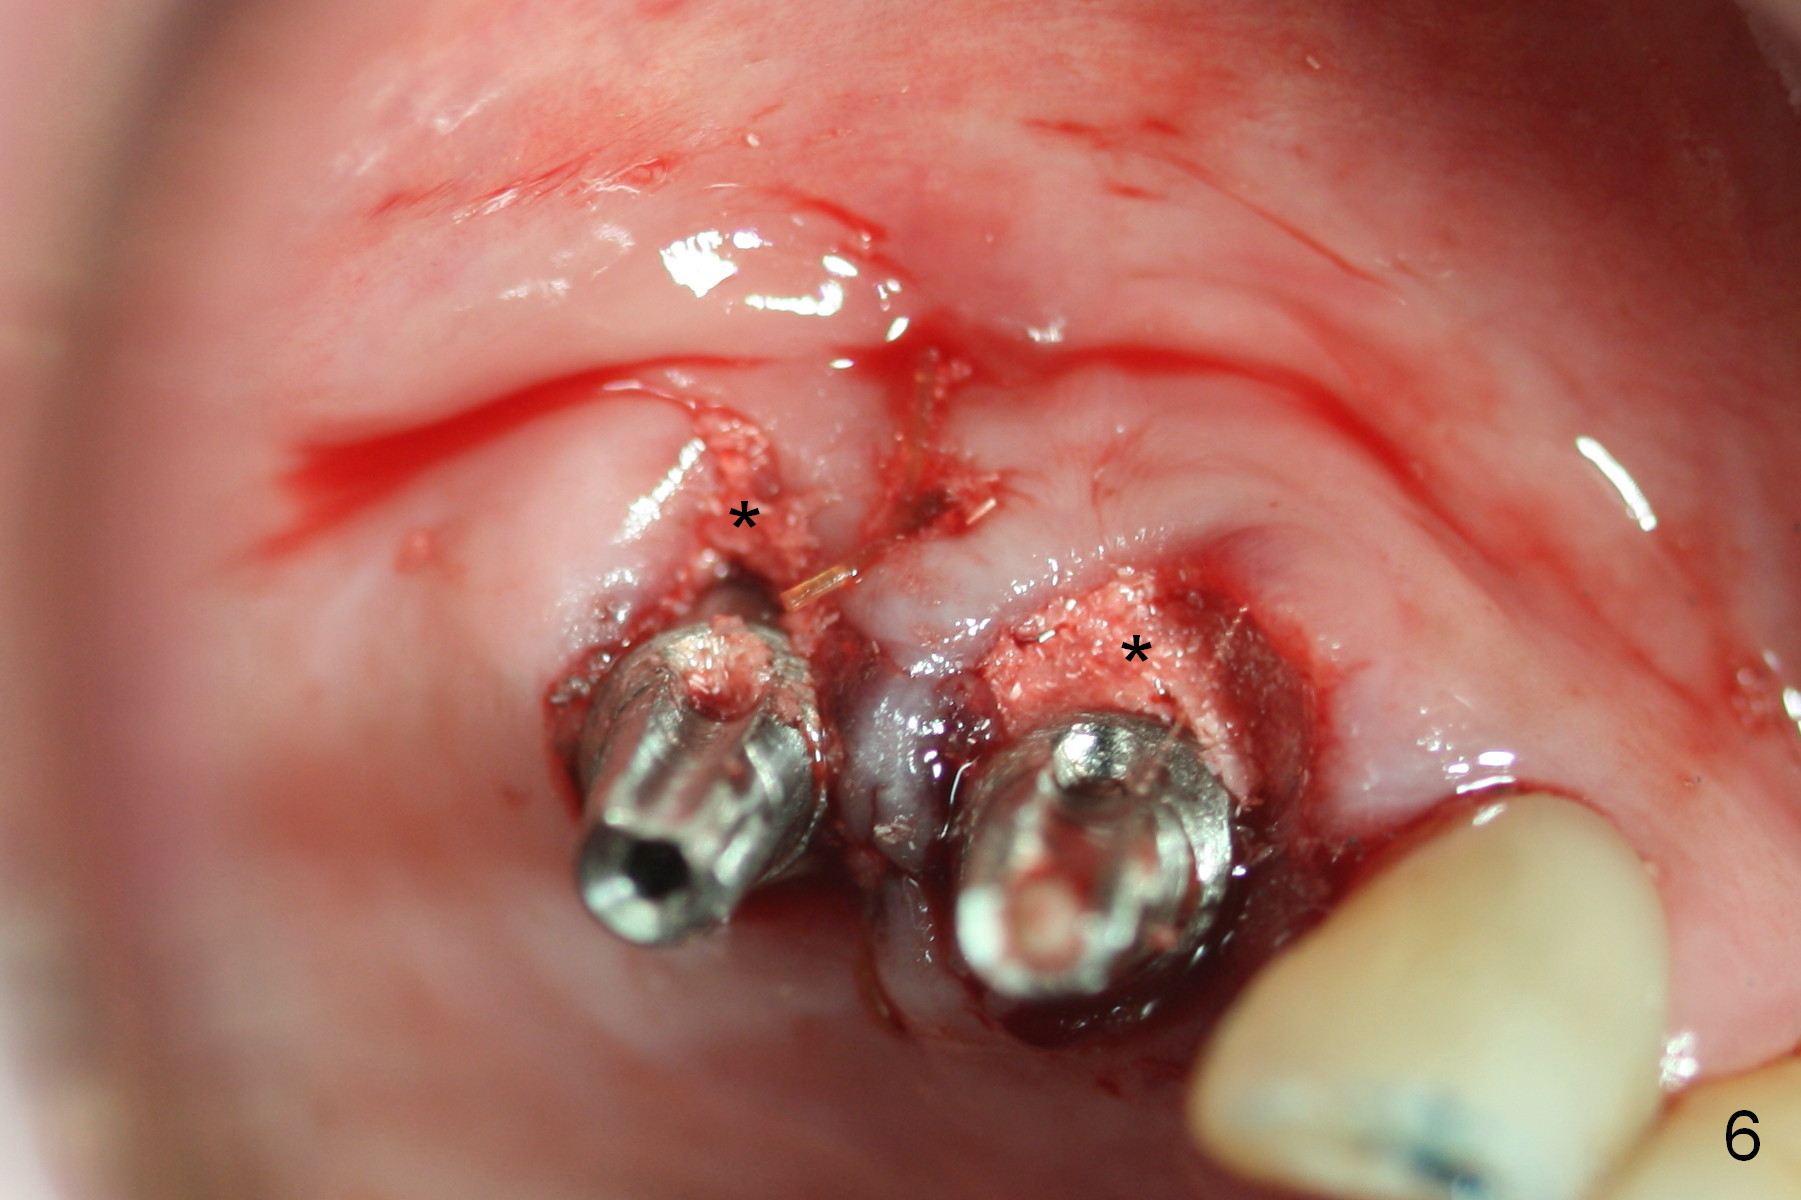

Several of CK's upper teeth (apparently in cross bite) are to be restored with implants (Fig.1).  The first two are #5 and 6; note the oval roots (Fig.2).  After extraction, and curettage, osteotomy starts in the palatal aspect of each socket.  The 1st intraop PA shows that the trajectory at #6 is incorrect (Fig.3).  After adjustment, osteotomies look parallel (Fig.4: D: 3.5x20 mm drill; T: 4.5x20 mm tap).  This suggests how important it is to use parallel pins to check initial osteotomies for neighboring implants (Fig.3).  The trajectory of the implants remains acceptable (Fig.5: 4.5x20 mm with insertion torque »60 Ncm); so is the position of the implants (as palatal as possible; Fig.6 (*: bone graft)).   Immediate provisionals are fabricated in cross bite.

Bone density in the distal gap of #5 appears to have increased 3 months postop (Fig.7).  Prior to definitive restoration cementation (3.5 months postop), the buccal plate does not collapse (Fig.8).  There is no occlusal contact of the new restorations (Fig.9 *), probably due to bite discrepancy (Fig.10,11).